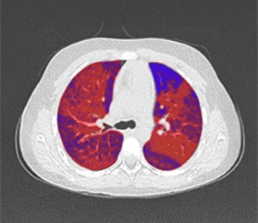

Quantitative assessment

Trapped air / Hyperinflation

Quantitative assessment

CT approximated perfusion defects

Quantitative assessment